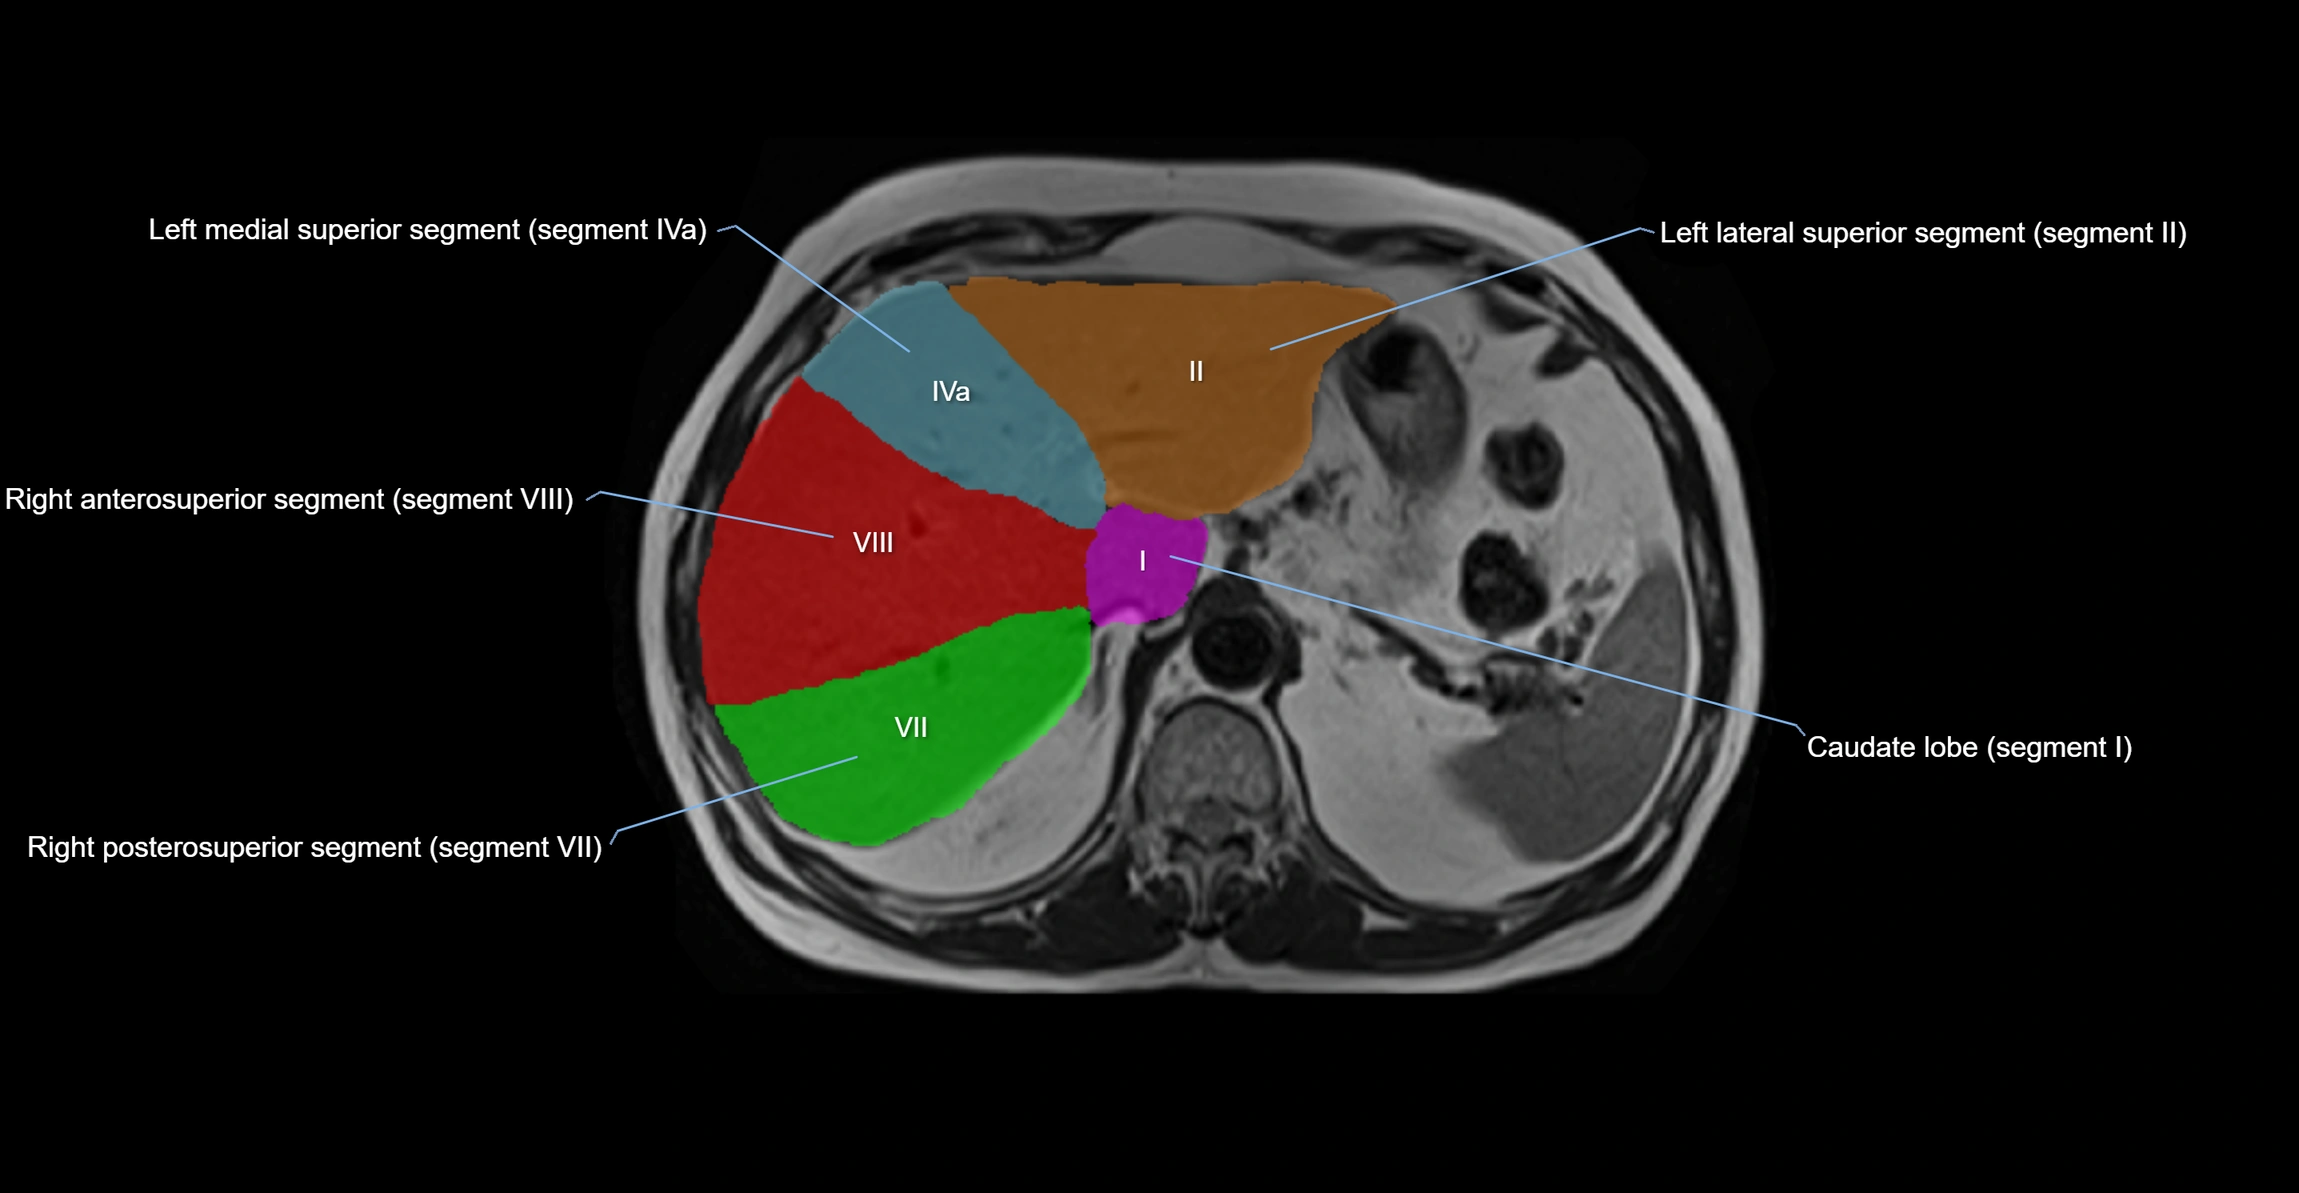

The caudate lobe of the liver is a distinct anatomical subdivision of the liver, designated as segment I in Couinaud’s classification. It lies on the posterior surface of the liver, between the fissure for the ligamentum venosum (left boundary) and the groove for the inferior vena cava (IVC) (right boundary). Superiorly, it is related to the posterior liver surface, and inferiorly it is separated from the left lobe by the porta hepatis.

The caudate lobe is unique because it receives dual portal venous and arterial inflow from both the right and left portal veins and hepatic arteries. It also has independent venous drainage directly into the IVC via multiple small hepatic veins, unlike other lobes that drain through the three main hepatic veins.

MRI image

image